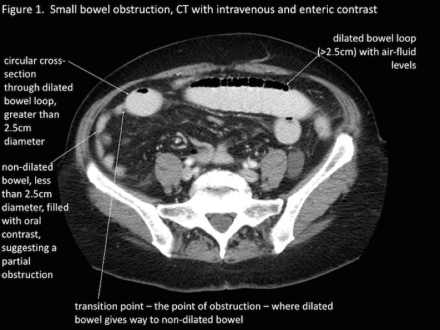

- Abdominal CT

- Much more sensitive and can also identify the specific causes

- Can also identify a transition point

- Other radiological signs on CT consistent with SBO include:

- Bowel wall thickening > 3mm

- Submucosal edema

- Mesenteric edema

- Ascites

- Target sign (intussusception)

- Whirl sign (volvulus)

- Venous cut-off sign (thrombosis)